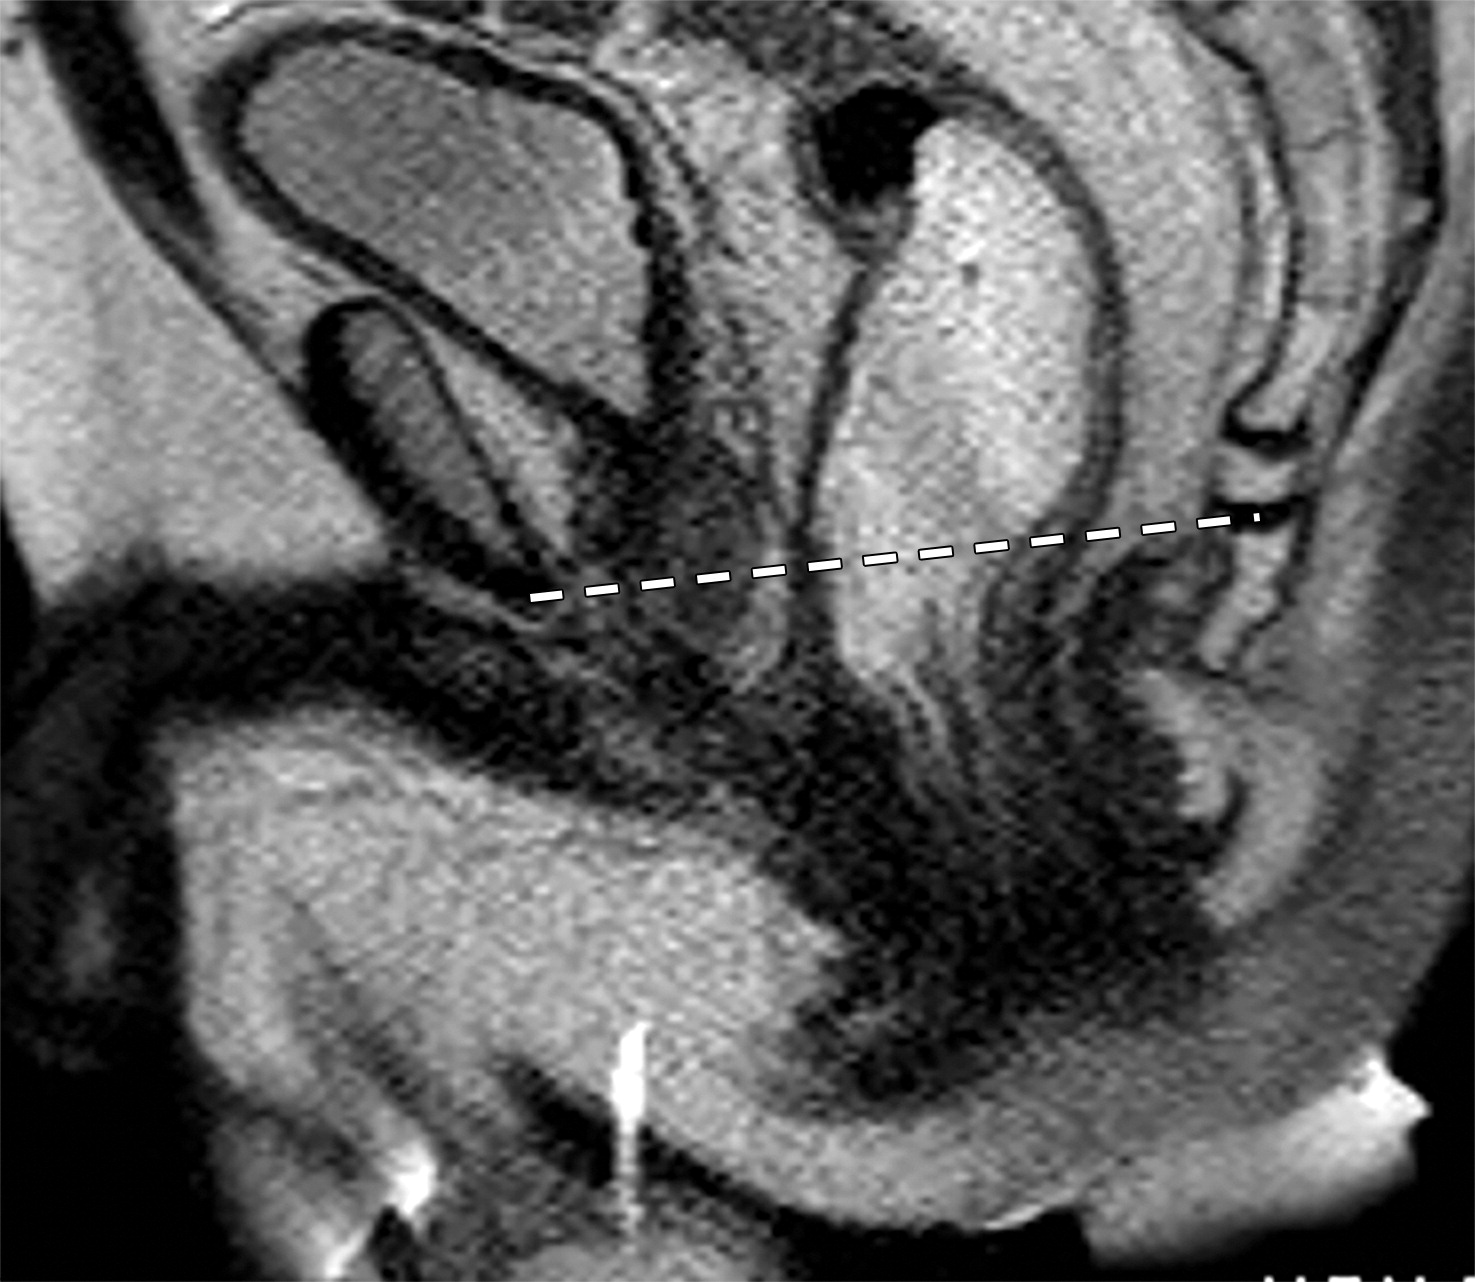

50岁以上男性骨盆和盆底的MRI解剖。

提肛肌(LA),由耻骨直肠肌(PR)、耻骨尾骨肌(PC)和髂尾骨肌(IC)组成;尾骨肌(C),前列腺(P),闭孔内肌(OI),会阴浅横肌(STP),球海绵体肌 (B), 坐骨海绵体肌(ISC),肛门外括约肌(EAS),肛门内括约肌(IAS),直肠(R),尿道括约肌(SU),也称为尿道外括约肌(U),它包围着整个膜性尿道。6774449af17bb1b8df6e83ab4e9fa158.jpeg